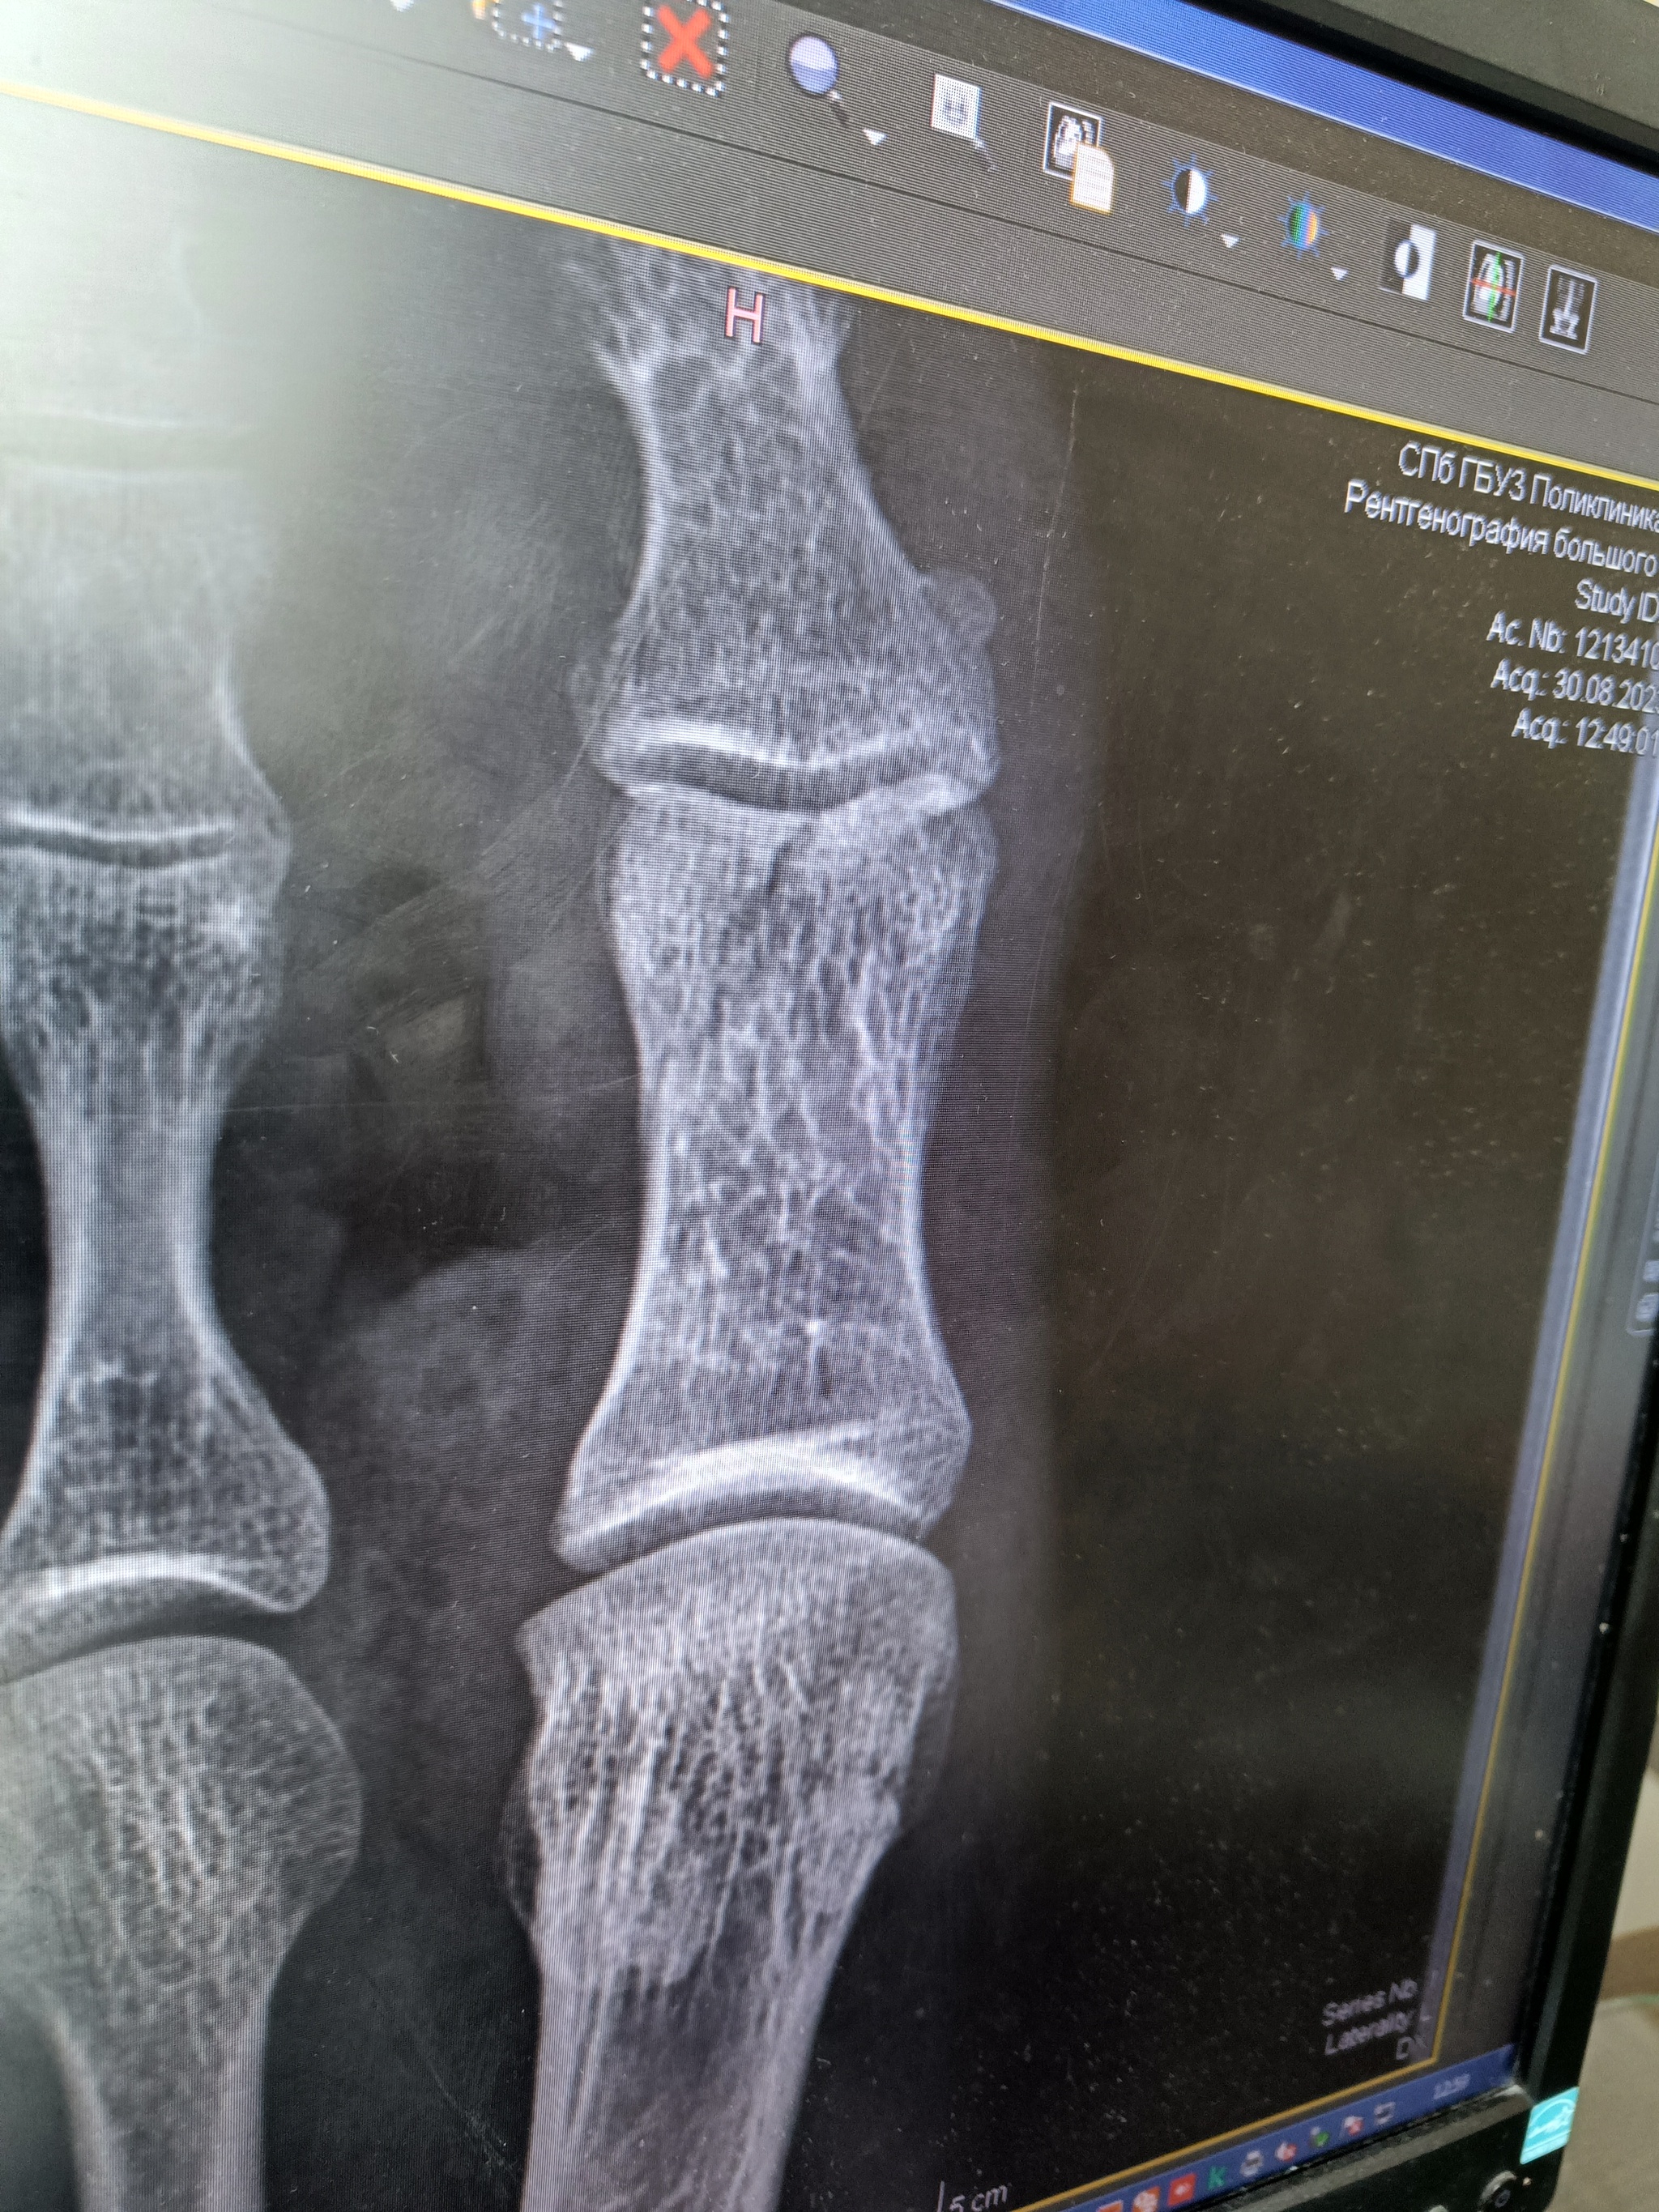

Очень хочу мотоцикл....далее Многа букв... был в двух мото авариях в детстве в Урале в люльке с соседским другом ехали с моря, батя синий уснул уехали в кювет кувыркнувшись пару раз по оси как сейчас помню как башкой земли касался сидя в люльке и линию горизонта которая менялась поочередно...два оборота точно сделали...встали на колеса, все живы...и вот я казалось бы взрослый, решил сдать на права будучи автолюбителем уже лет как 8... Сдал, а все без мотоцикла... Прошло ещё 7 лет, я по прежнему без Мота но дико хочу его иметь....поехал в Питер в 23году решил взять в прокат, Питер не знал, взял чоппер какой-то японский Honda NV750 2001года...Мот мне понравился единственно грелся периодически, позвонив в прокат, мне там посоветовали его побольше "крутить", все поехал, навигация 2гис и наушник в ухо...из защиты только шлем, кожаная куртка и обычные брюки с кросами.... Взял в ночь в надежде на малый трафик, довольный был до соплей, катал буквально куда глаза глядят... И вот решил, что накатался нужно отвозить мотоцикл на родину и ехать домой спать... Катал примерно часа три...и вот еду я такой деловой весь довольный собой и в параллель с машиной такси на какой-то мост эстакадный заходим... Скорость порядка 60... Смотрю мокро, в впереди поливалка прошла и сразу в подъем резкий поворот ....тут Астап немного растерялся и начал паниковать смотря в бордюр .... Не помню как тормозил и чем...в общем Мот я удержал, но протерся о бордюр метров 20... Думал все себе выверну и ногу левую и пальцы левой руки... Притерся знатно...и.... барабанная дробь никто из потока не остановился))) мало ли подумали каскадёр работает🤣 в общем сломал много чё по моту, вмял бак хорошенько... Собрал весь пластик который нашел в кофры...не нашел только лапку сцепления.... Отвёз самостоятельно Мот где брал и по утру в больницу т.к. прихрамывать начал... Как итог около 60к на ремонт мото... Подранная куртка , брюки, кроссы, сломанная на ноге фаланга большого пальца, немного пожеванная кисть руки левой, пару шрамов на левой ноге чуть ниже колена , подранный голеностоп и куча эмоций... Вы наверное подумали что мотоцикл я перехотел ?! Ничего подобного....по прежнему сплю и вижу....